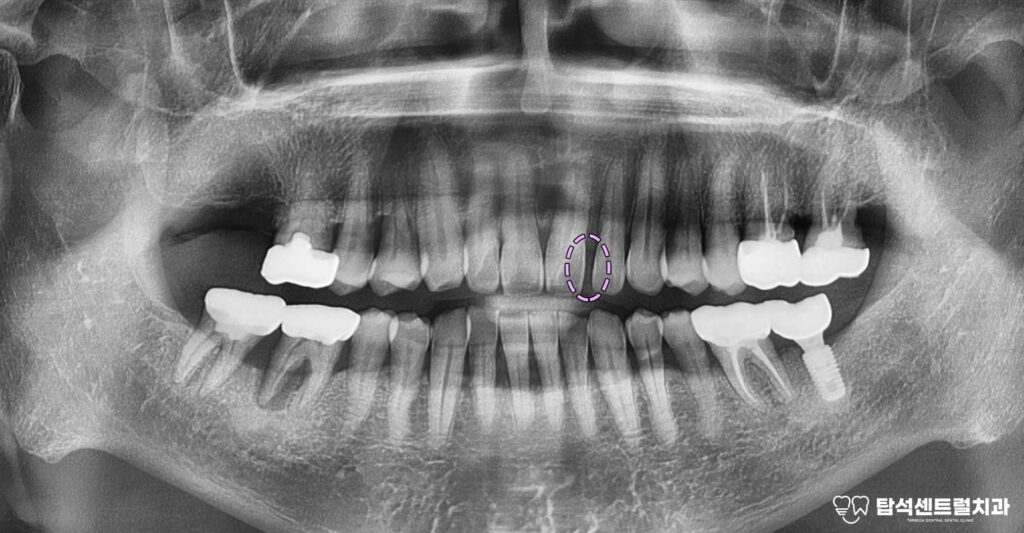

벌어진 앞니 사이 공간, 어떻게 개선할 수 있을까

벌어진 앞니 사이에 공간이 있으면

발음할 때 공기가 새어나가

의사소통에 어려움이 생길 수 있습니다.

혹은, 치아와 턱뼈의 크기가

균형을 이루지 못하는 경우

사이에 비어 있는 공간이 생깁니다.

턱뼈가 이에 비해 큰 경우나

선천적으로 개수가 부족하다면

이런 현상이 나타날 수 있습니다.

교합 관계가 맞지 않거나

잇몸 질환으로 인해

치조골이 약해진 경우에도

이가 이동하면서

공간이 발생하기도 합니다.